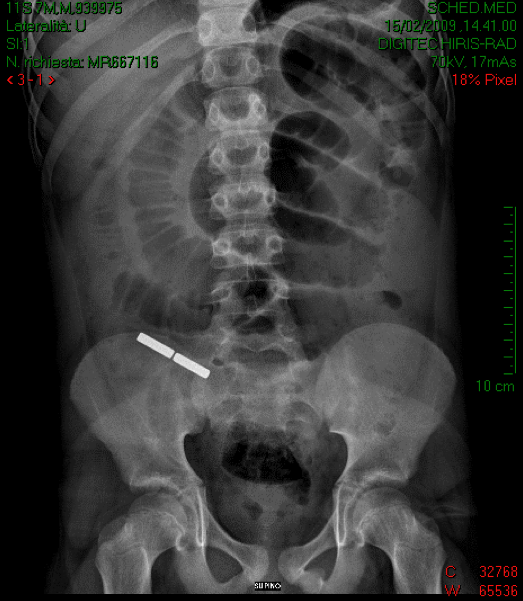

ectasiche. L'Rx addome di controllo mostra poi la presenza di

un altro corpo estraneo metallico, analogo a quello rimosso in

sala operatoria, proiettantesi sul sacro, che viene poi espulso

spontaneamente in 10° giornata post-operatoria (Figura

2).

![]()

Figura

2